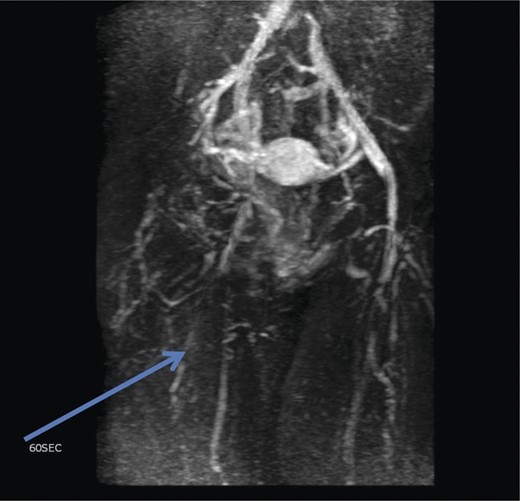

Initial investigations included duplex scan, followed by magnetic resonance scan. Duplex scanning demonstrated a competent sapheno-femoral (SFJ) and Sapheno-popliteal (SPJ) junctions bilaterally; however, did raise suspicion of a pelvic origin of the vulval varices with congested pelvic veins. Magnetic resonance venogram aided the diagnosis by demonstrating the communication of the vulval varices to the upper thigh veins with contribution from the internal iliac vein. In this case there was no evidence of ovarian varices (Fig. 1). Catheter venography was unable to confirm the contributing vein with certainty but computed pelvic venography showed a likely connection through the superficial external pudendal vein (Fig. 2).

Magnetic resonance venogram showing communication of thigh veins to vulval varices (blue arrow).